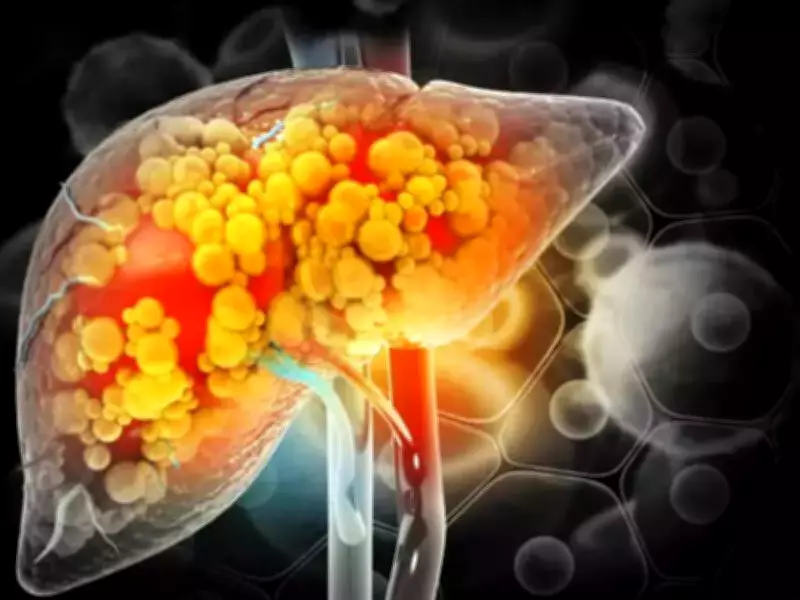

The liver damage in diabetic patients is fueled by hepatic insulin resistance, a condition where fat accumulation causes the liver to stop responding to insulin properly. This triggers chronic inflammation that leads to permanent scarring over time.

What makes this complication particularly dangerous is its silent nature. The liver rarely produces noticeable symptoms until it is nearing failure, meaning patients can progress toward life-threatening liver failure without showing any outward signs of distress.

This phenomenon is known as "burnt-out" liver disease, where fat disappears as scarring worsens, leaving the organ shrunken and non-functional. In these "fat-light" cases, age and the cumulative toll of high blood sugar over decades emerged as the primary predictors of damage.